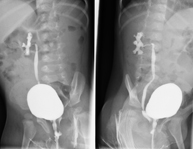

- Voiding Cystourethrography (VCUG)

Serial voiding cystourethrography involves radiological imaging to assess the anatomy and function of the urethra and bladder with the administration of iodinated contrast through a bladder catheter.

- Urethrocystography (Urethro-CG)

Retrograde-minctional urethrocystrography involves radiological imaging to assess the anatomy and function of the bladder and urethra. Contrast material is applied through a small catheter placed in the urethra and images are obtained during the filling and emptying of the bladder.